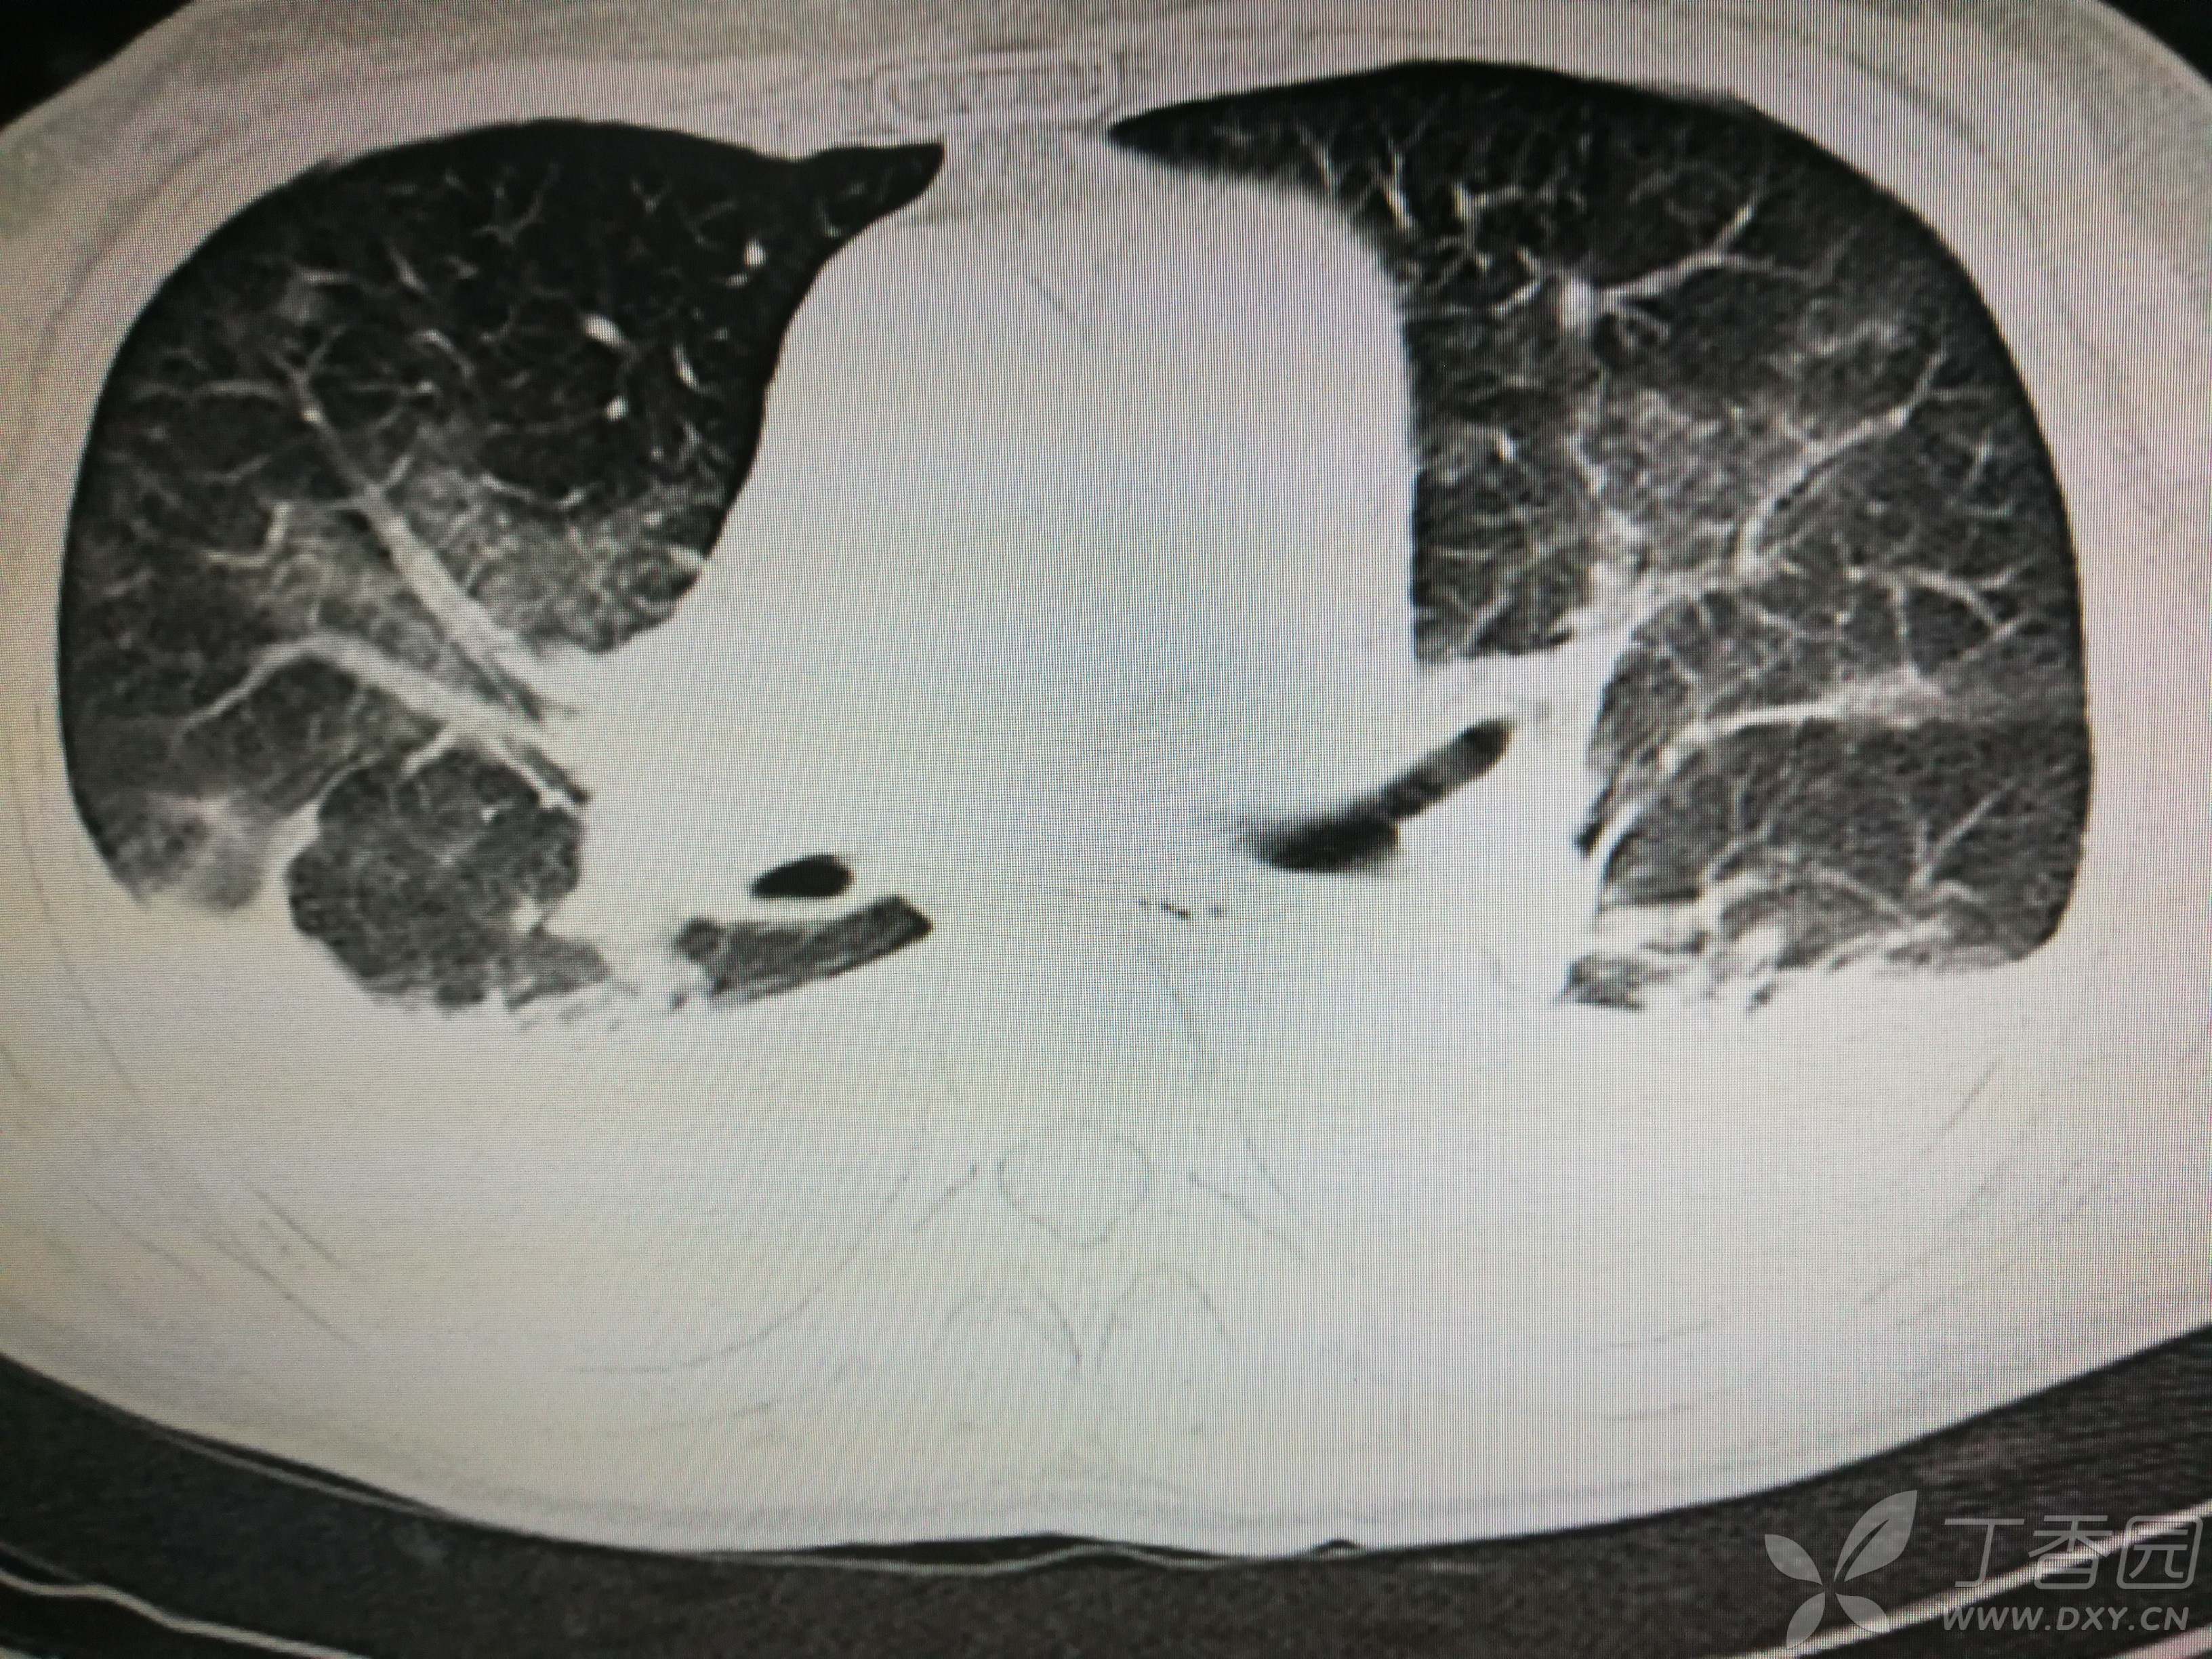

给予低分子肝素钙针抗凝、七叶皂苷钠针消肿及骨牵引固定等等治疗。入院后第四天行“左侧股骨下段骨折切开复位内固定术”(术前查双下肢彩超:双下肢深静脉血流通畅),手术顺利,术后予预防感染、预防血栓形成等治疗。术后患者无明显发热,生命体征平稳。术后第四天复查血常规:白细胞13.4×109/L,血红蛋白84g/L,血小板在正常范围。生化:白蛋白35.7g/L,余无明显异常。当天,患者开始出现轻度胸闷气急,可耐受。术后第五天患者胸闷气急加重,无胸痛,无背痛,无咯血,无意识障碍,无头晕头痛,无恶心呕吐等,急查凝血功能:纤维蛋白原降解产物12mg/L,D二聚体4000ug/L,余无明显异常。查动脉血气分析:pH7.52,氧分压62mmHg,二氧化碳分压30mmHg,碱剩余1.8mmol/L,乳酸1.0mm/L,血红蛋白86g/L。查胸部CT见下(先视频后图片):